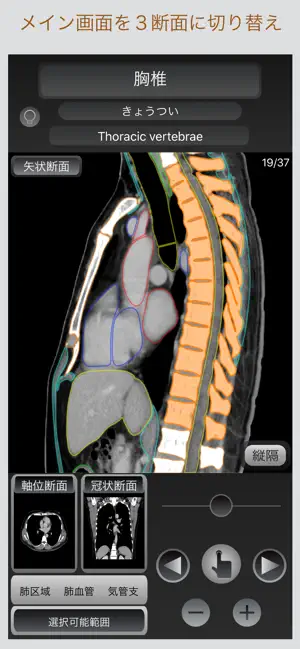

このアプリでは、画像に触れるだけでその解剖名称を表示し、すぐに目的とする箇所を調べられるだけでなく、軸位断面・冠状断面・矢状断面の切り替え表示が可能であり、選択部位の位置関係を瞬時に把握することが出来ます。

■断面の切り替え表示

サブ画面を選択する事で、目的の断面と切り替え表示が可能です。

■肺野・縦隔の表示

肺野・縦隔の切り替えが出来ます。